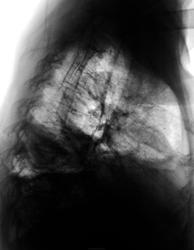

Неделю лечится в терапии, как бы по поводу сердца...

это пиопневмоторакс? или только жидкость в легком? а слева на уровне дуги аорты что? нет ли там чего-нибудь посерьезней, чем инфекция?

Хочется переломов рёбер, ключицы, всё справа, но как-то не очень внятно... а жаль!smiley Тогда причина и следствие так аккуратно вписывались бы в картину!

А это в плевре, или, скорее, в легком? Эмпиема, или абсцесс?

клиники эмпиемы нет,осумкованный пневмоплеврит.

1.Пневмоплеврит (pneumopleuritis; пневмо‑ (Пневмо-) + Плеврит) экссудативный плеврит, при котором в плевральной полости наряду с экссудатом скапливается воздух; развивается при наличии бронхоплеврального свища или как осложнение искусственного пневмоторакса.

2.Эмпиема плевры (пиоторакс, гнойный плеврит) — скопление гноя в плевральной полости. Как правило, эмпиема плевры развивается в связи с инфекционным поражением лёгких (пневмонией) и часто ассоциирована с парапневмоническим выпотом. Различают три стадии эмпиемы: экссудативная, фибринозно-гнойная и организующая. При экссудативной фазе происходит накопление гноя. Фибринозно-гнойная стадия проявляется осумкованием плевральной жидкости с формированием гнойных карманов. В конечную, организующую стадию, происходит рубцевание плевральной полости, которое может привести к замуровыванию лёгкого.

Как то не очень это на пневмоплеврит смахивает. да и где соответствующий анамнез?

А клиника может быть разной, ведь эмпиема может быть и хронической.

гидропневмоторакс справа , смещение горизонтальной м/д щели кверху , левый рёберно-диафрагмальный синус уплощён - нельзя искл. небольшое кол-во жидкости и в левой плевральной полости.

Травмы не было.

Вы правы уважаемый Виктор Григорьевич!

"Это" мало смахивает на пневмоплеврит, ну просто, аж никак.

Если не было пункции, то откуда воздух? Или из бронха (деструкция), или сами бактерии вырабатывают. В любом случае похоже на эмпиему.

Пневмогидроторакс осумкованный, эмпиемы клиника несоответствует. В месте темном мы оказались… Знания осветили бы наш путь. Темной стороны страшусь я.

Рак плевры? Взять жидкость на цитологию!